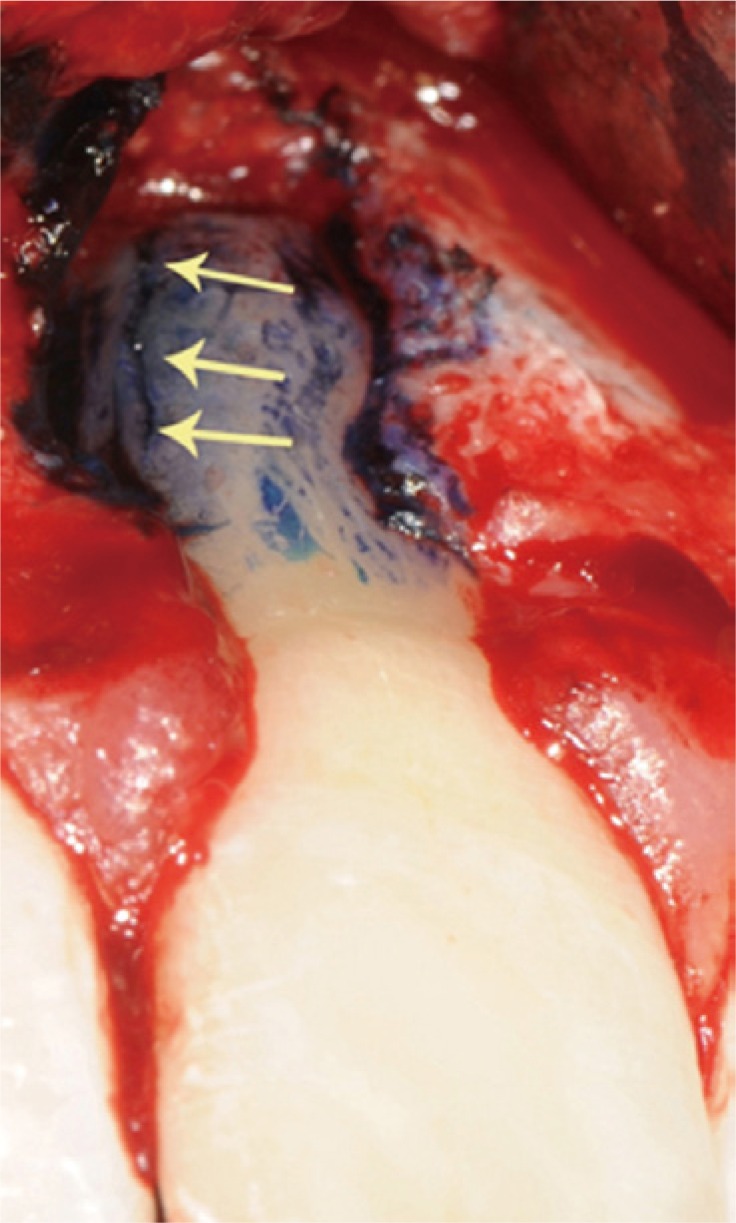

A clinical examination showed a moderate swelling on the vestibular side in the region of tooth #21, as well as the presence of a sinus tract in the same area, approximately 4 mm from the gingival margin (Figure 1). A narrow periodontal defect 7 mm in depth was present on the buccal side, as evaluated using a periodontal probe. A radiographic examination performed before surgery using both periapical radiographs and CBCT (J. Morita MFG Corp., Kyoto, Japan) revealed a root-end resection, a periapical radiolucency, and a widening of the periodontal ligament space at the mesial aspect of the root, although no hair-like fracture line radiolucency was noted in the tooth, except in the CBCT horizontal projection that showed an incomplete VRF 3 mm from the apex (Figure 2).